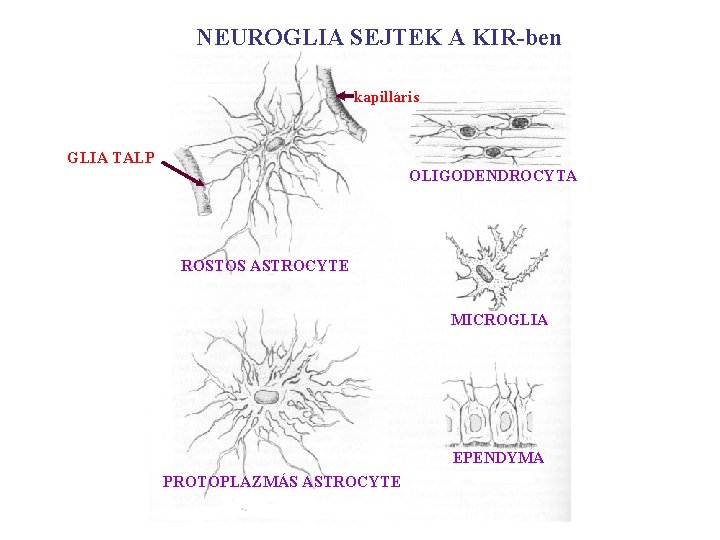

NEUROGLIA SEJTEK A KIR-ben kapilláris GLIA TALP OLIGODENDROCYTA ROSTOS ASTROCYTE MICROGLIA EPENDYMA PROTOPLAZMÁS ASTROCYTE